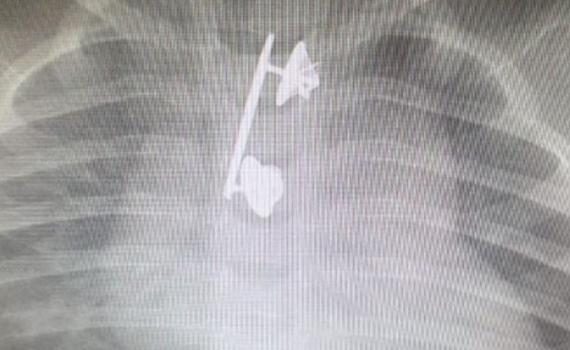

ההורים המודאגים פינו אותו לבית החולים, שם למרבה התדהמה, התגלה לאחר צילום רנטגן כי בוושת שלו תקועה סיכת מ"מ של אימו הקצינה. הסיכה הוצאה בניתוח והתינוק שוחרר לביתו לאחר מספר ימים.

ד"ר מיכל קורי וד"ר מאיר וורמן, שני הרופאים ששלפו בהצלחה את הגוף הזר מהוושט, סיפרו: "כאשר נתגלתה סיכת המ"מ בצילום היה ברור שהפרוצדורה תהיה מאוד מורכבת בשל הגודל והחדות של שלה. העובדה שהסיכה הוצאה בזמן מנעה סיכונים שעלולים להיגרם במקרים אלו כגון קרע של הושט, זיהום וקשיי בליעה. אין ספק שערנות ההורים במקרה זה הייתה בעלת חשיבות רבה".